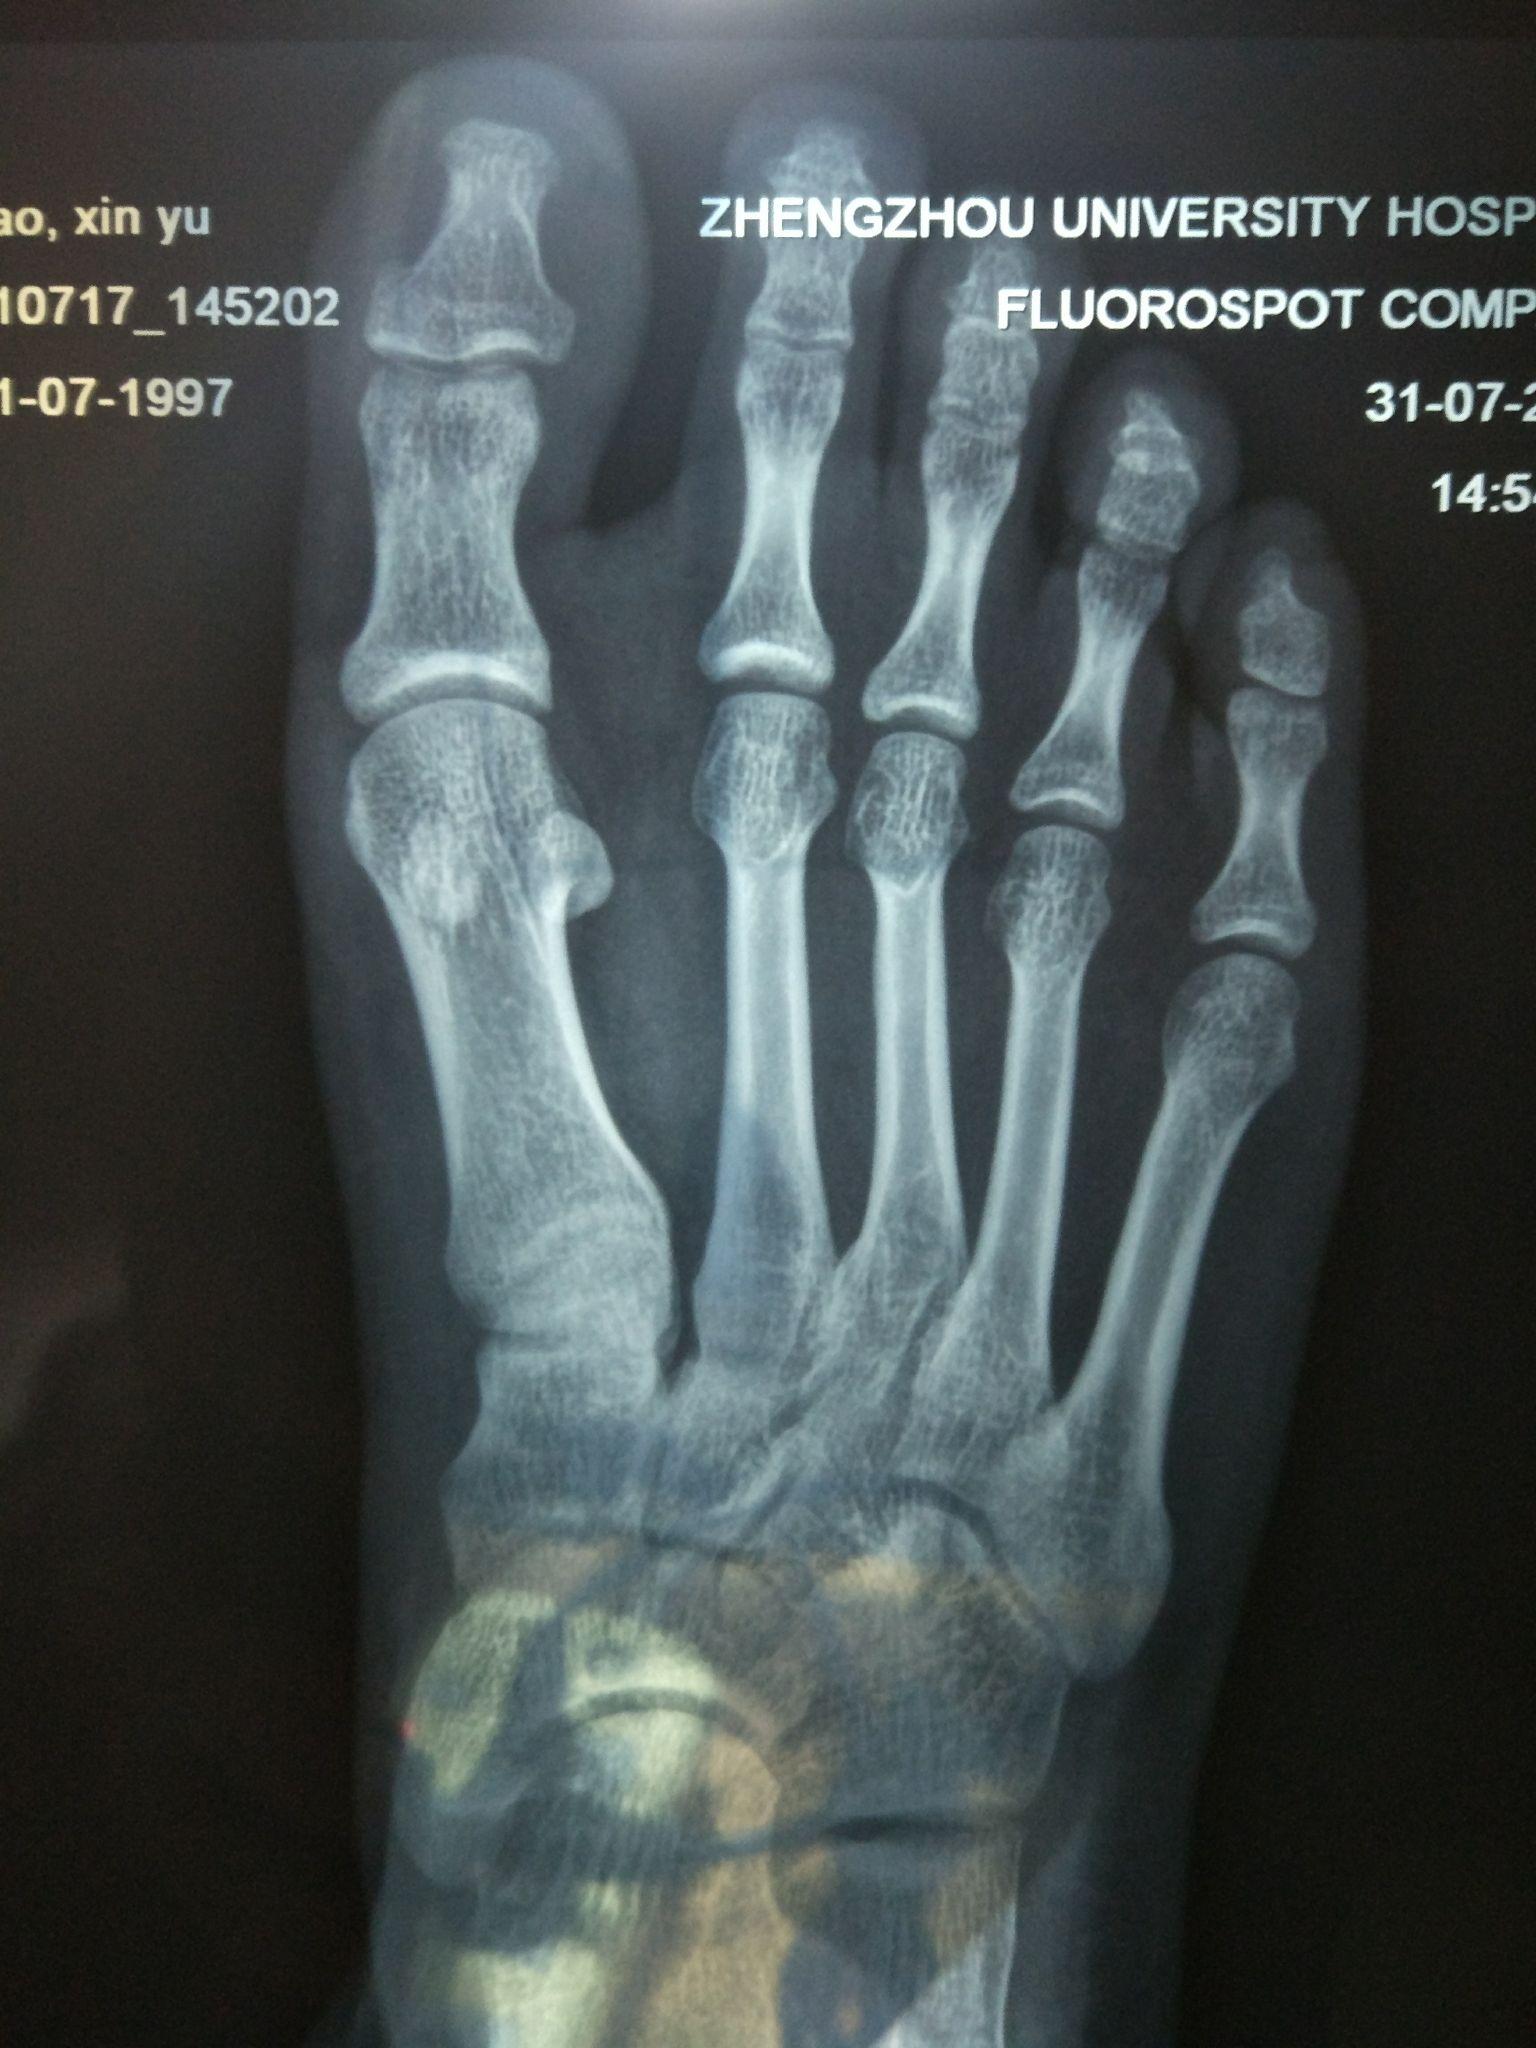

个人认为这是谣言,有图为证,下面是我隔壁室友拍的脚部X光。请大家数一数,真的少了一截骨头吗?至于说什么个体不能代表全部,我只能无言以对。

1、中国人的脚趾骨骼数量,第七军医大学发表在《解剖学报》1963年03期上的文章(万玉碧:中国人第三、四、五趾趾骨数目的观察)统计得出:第五趾有两个趾骨者,占73.34±1.77%;第四趾占13.18±1.36%。在294只足中,第三趾有两个趾骨者,占3.43±1.06%

2、至于其他族群:2001年的一篇文献“Biphalangeal fifth toe: an increasingly common variant?”[doi: 10.1046/j.1469-7580.2001.19820251.x] 里面提到欧洲人中有35.5%(Venning,1960),日本人80.4%(Thompson &Chang)的第五个脚趾是只有两个骨头的。来自知乎用户 @阿Shay

由此可见,绝大多数东亚人的第五趾是两个趾骨,与其他族群不同。

第5趾远节趾骨甚小,常与中节趾骨融合,虽然常融合,但实际上第五趾远节趾骨还是存在的

至于白种人第五趾远节趾骨是不是不常融合,那就不知道了

室友的X光算是证明了确实如此。